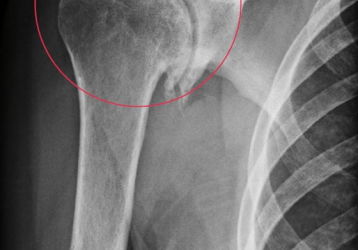

Вывих плеча: причины травм, симптомы и варианты лечения

Вывих плечевого сустава(плеча): признаки, причины, диагностика. Привычный вывих плечевого сустава. Первая помощь и методы лечения травм плечевого сустава.